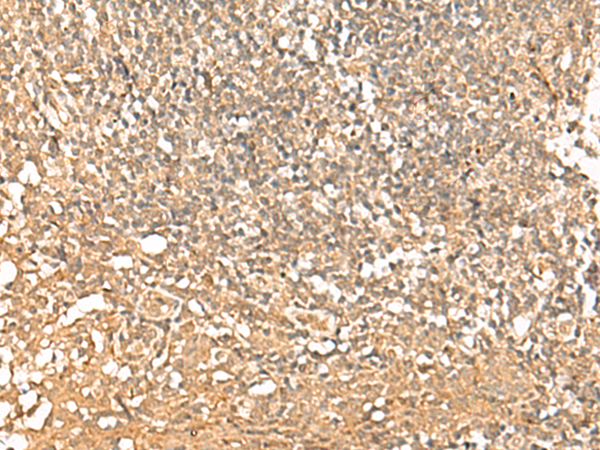

IHC positive control:

Human tonsil

IHC Recommend dilution:

50-300